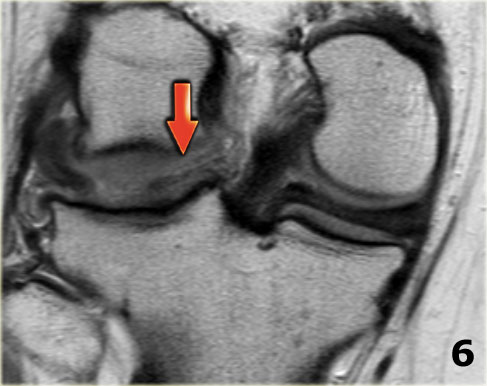

Bên trái là các hình ảnh PD sagittal của một trường hợp sụn chêm lật.

Toàn bộ sừng sau bị lật ra phía trước, tạo ra dấu hiệu sụn chêm rỗng (empty meniscus sign) (mũi tên).